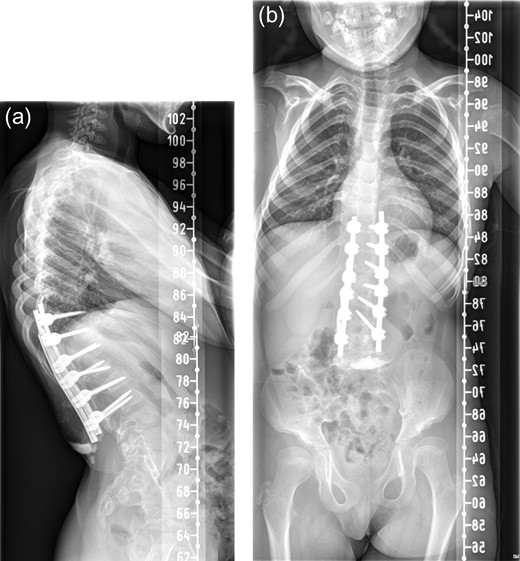

There was serous discharge with flakes of i-Factor in the drain postoperatively. Wound drain was removed on the second day and postoperative radiograph (Fig. 2) was satisfactory. Patient was discharged with a dry wound on the fifth day. Patient reattended hospital on seventh day with serous discharge from the drain site. There was no sign of infection and the wound was covered with a PICOTM dressing (Smith and Nephew), a negative pressure wound therapy system. At Day 10 the primary wound was healed, but serous fluid containing i-Factor flakes noted from the drain site. Patient was not started on antibiotics as there was no sign of infection and blood markers were normal. Wound was kept covered with a dressing and the discharge stopped.